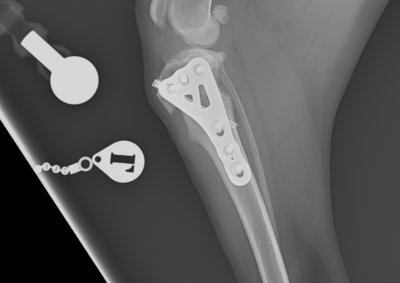

整形外科 注意 ボタンをクリックした先に、治療中および手術中の画像が説明で使用されている場合がございます。 そのような画像に弱い方は閲覧なさらないようお願いいたします。 整形外科 上腕骨外顆骨折の癒合不全 整形外科 大腿骨遠位開放および粉砕骨折 整形外科 膝蓋骨内方脱臼+前十字靭帯断裂 PGR#21+CBLO #251 整形外科 犬の前十字靭帯断裂に対するCBLO #250 整形外科 脛骨粉砕骨折 整形外科 内側鉤状突起分離症(Fragmented Medial Coronoid Process:F... 整形外科 股関節全置換術(トータル・ヒップ・リプレイスメント)#27 整形外科 橈骨固定術 #268 整形外科 橈骨固定術 #267 整形外科 橈骨固定術 #266 整形外科 股関節脱臼に対するBUSTOR #67 整形外科 脛骨粗面剥離骨折 <1234567> 症例カテゴリー 放射線治療整形外科軟部組織外科脳神経外科内科腫瘍外科救急・集中治療リハビリテーション科腫瘍内科内視鏡科脳神経科呼吸器外科中医・漢方猫の腎移植循環器科